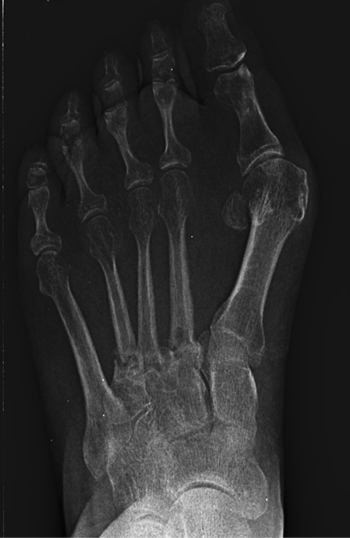

Se realizó radiografía dorso-plantar en carga del pie derecho (Figura 1) que mostraba una imagen radiológica compatible con ausencia de consolidación de las osteotomías en las bases de 2.º, 3.º y 4.º metatarsianos, además de la presencia de hallux abductus valgus. Se solicitó una tomografía axial computarizada (TAC) para estudiar más detenidamente el estado actual del proceso de consolidación ósea. La paciente acudió con resultado de TAC el 5 de mayo de 2015, donde se evidenció la ausencia completa de consolidación ósea en segundo metatarsiano (Figuras 2A y 2B), consolidación prácticamente completa de tercer metatarsiano (Figura 2C) y la presencia de callo óseo con consolidación incompleta en el cuatro metatarsiano (Figura 2D).

Figura 1. Radiografía dorso-plantar en carga del pie derecho. Se evidencia la ausencia de consolidación de las osteotomías en las bases de 2.º, 3.º y 4.º metatarsianos después de 9 meses de la intervención inicial.